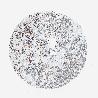

LIVER CANCER - Protein expressioni

A mouse-over function shows sample information and annotation data. Click on an image to view it in a full screen mode. Samples can be filtered based on level of antibody staining by selecting one or several of the following categories: high, medium, low and not detected. The assay and annotation is described here.

Note that samples used for immunohistochemistry by the Human Protein Atlas do not correspond to samples in the TCGA dataset.

Antibody stainingi

Antibody staining in the annotated cell types in the current human tissue is reported as not detected, low, medium, or high, based on conventional immunohistochemistry profiling in selected tissues. This score is based on the combination of the staining intensity and fraction of stained cells.

Each image is clickable and will lead to virtual microscopy that enables deeper exploration of all samples and also displays staining intensity scores, fraction scores and subcellular localization as well as patient and tissue information for each sample.

Antibody HPA048677

Antibody HPA056480

Antibody CAB011574

Staining

High

Medium

Low

Not detected

Intensity

Strong

Moderate

Weak

Negative

Quantity

>75%

75%-25%

<25%

None

Location

Nuclear

Cytoplasmic/membranous

Cytoplasmic/membranous,nuclear

Carcinoma, Hepatocellular, NOS